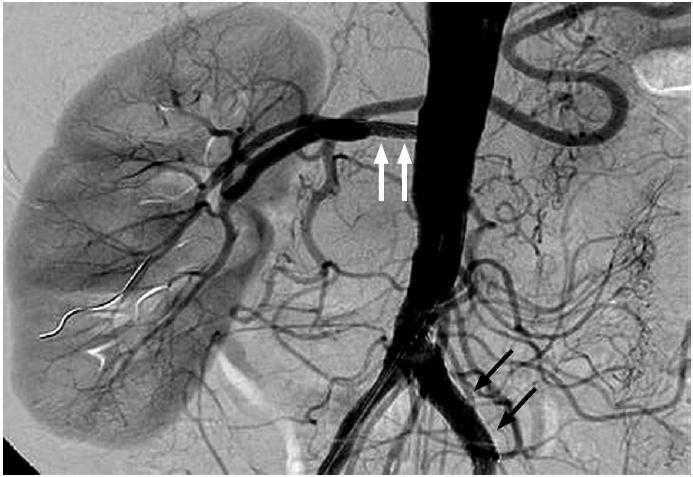

Los resultados de la arteriografía están en la Figura 1. Se colocan 2 stents (Figura 2) y la paciente evoluciona satisfactoriamente y permanece asintomática con normalización de la tensión arterial sin precisar medicación y mejoría de la función renal (Crs 1,1 mg/dL).

Figura 1. A) Riñón izquierdo hipoplásico con oclusión completa de la arteria renal izquierda con revascularización distal mediante circulación colateral; B) Estenosis severa a nivel del ostium y porción proximal de la arteria renal derecha de aproximadamente un 70%